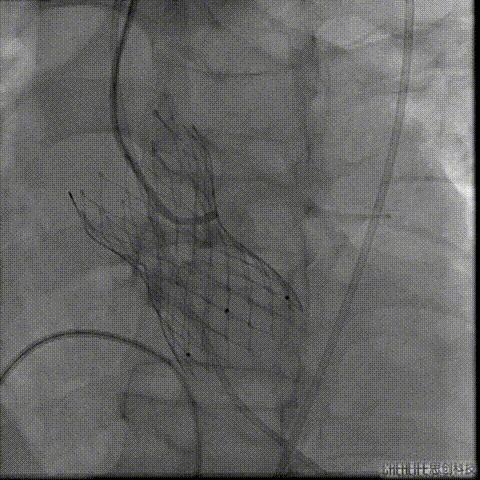

经桡冠脉保护

置入Venus-A32号瓣膜并释放

复查造影

撤出冠脉保护

再次复查造影

经瓣架网眼挂上指引管

反复确认指引管经瓣架网眼

指引管经瓣架网眼

经网眼置入导丝

置入4.0mm*23mm微创冠脉支架

定位并释放支架

退出球囊扩张突入瓣架部位

复查冠脉造影

多体位复查冠脉造影